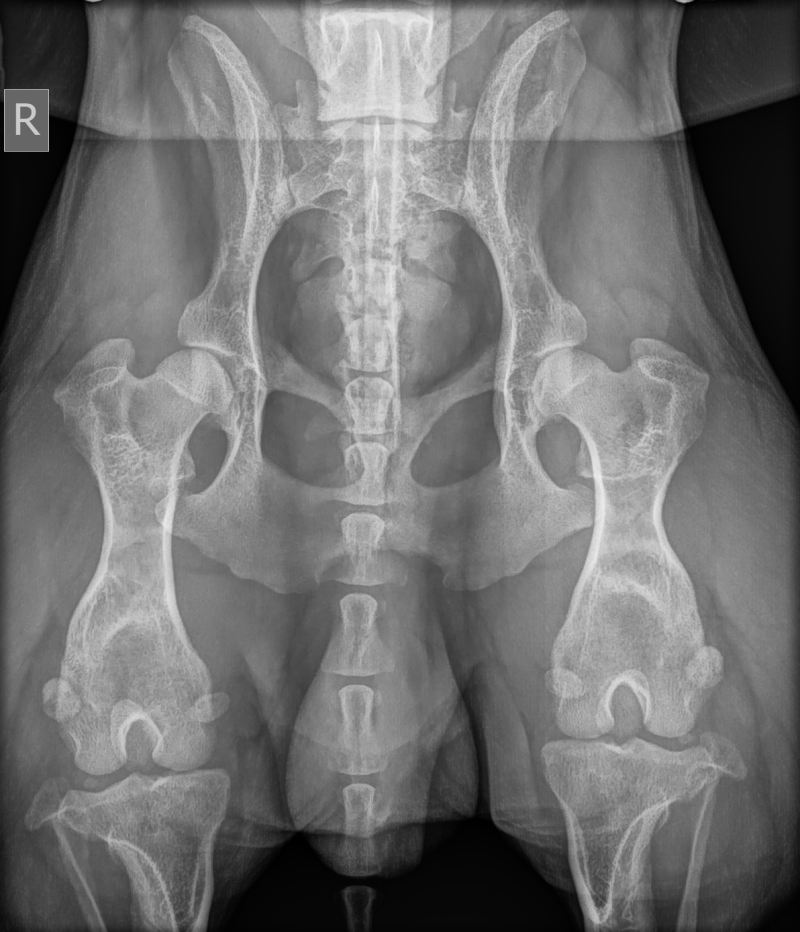

- Dysplasie de la hanche : OFA GOOD - FCI HD gauche B / droite C (sous anesthésie à l'université de Gand)

- Laxité des hanches : VMBDD gauche LI 0,30–0,49, droite LI 0,50–0,69

- Luxation de la rotule : ok

- Dysplasie du coude : FCI ED 0/0 (sous anesthésie)